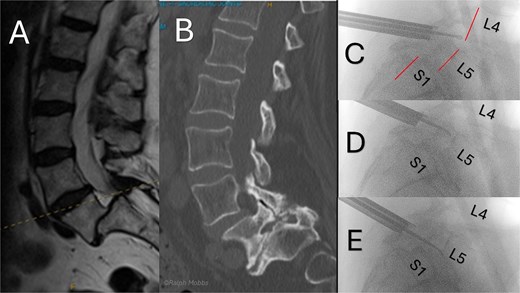

Imaging demonstrated stable borderline Grade III L5/S1 degenerative spondylolisthesis with facet hypertrophy, severe foraminal stenosis and lateral recess narrowing (Fig. 3). Following multidisciplinary review, right interlaminar uniportal endoscopic decompression with conscious sedation was undertaken. The hypertrophic superior and inferior articular process at L5/S1 and flavum were excised with unilateral endoscopic decompression on the symptomatic side, without violating the contralateral facet.

Preoperative and intraoperative imaging of case 3. (A) Sagittal T2-weigthed MRI demonstrating grade II+ degenerative spondylolisthesis at the L5/S1 level. (B) Sagittal CT demonstrating severe foraminal stenosis at L5/S1. (C–E) Intraoperative fluoroscopic images showing placement of the working channel and guidewire using forceps for targeted decompression.

He walked 3 hours post-op and was discharged on the same day. At 6-week review VAS was 2–3/10, with return to work within 2 weeks. At 3 months VAS 1–2/10 and repeat standing radiographs confirmed unchanged slip, with no instability. At the time of this report he remains with significant symptom reduction, uses minimal analgesics and expresses no desire for fusion. Annual surveillance imaging is planned.